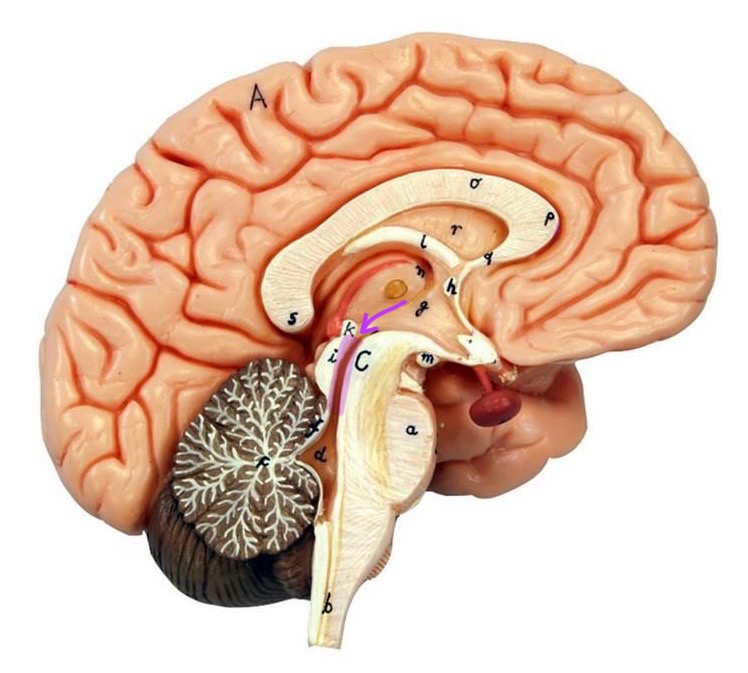

What is D?

lateral ventricle

Imagine thin membrane separating the 2 lateral ventricles

septum pellucidum

What is C?

3rd ventricle

What is B?

cerebral aqueduct

What is A?

4th ventricle

What is below A at the very end?

central canal (spinal cord)

What is C?

midbrain

tectum (corpora quadrigemina): superior colliculus

tectum (corpora quadrigemina): inferior colliculus

What is a?

pons

medulla oblongata

intermediate mass of thalamus

hypothalamus

What is the pink bulb?

pineal gland

corpus callosum

fornix

What is A?

cerebral cortex

cerebral tracts

cerebral hemispheres

longitudinal fissure

What are these ridges?

gyri

What are these shallow grooves?

sulci

Divides parietal from frontal lobe

central sulcus

precentral gyrus

postcentral gyrus